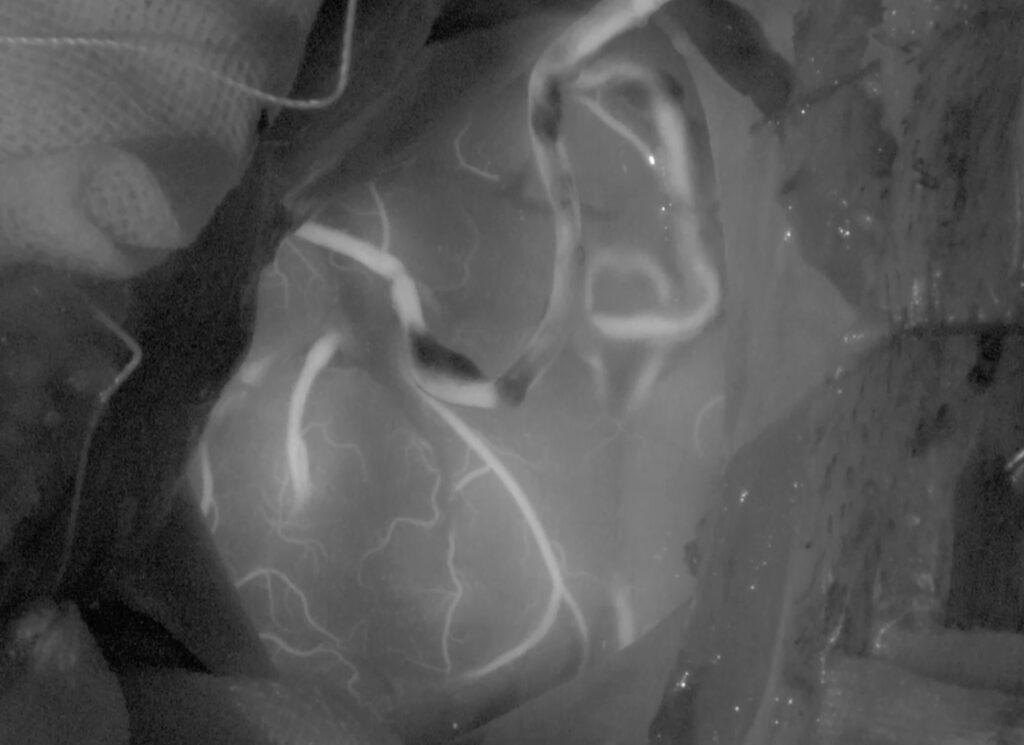

左海綿静脈洞内髄膜腫(複視)に対して、現在のスタンダードは放射線治療になりつつありますが、これも長期制御が困難なので、今回はBTOで左内頸動脈閉塞による血管内腫瘍塞栓を行う計画としました。それに先立ち、BTO時のStump <50mHgであったためSTA-MCAバイパスを行いました。